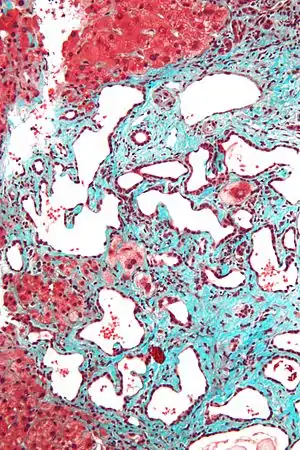

Micrograph of a bile duct hamartoma. Trichrome stain.

Low magnification micrograph of a bile duct hamartoma. Trichrome stain.